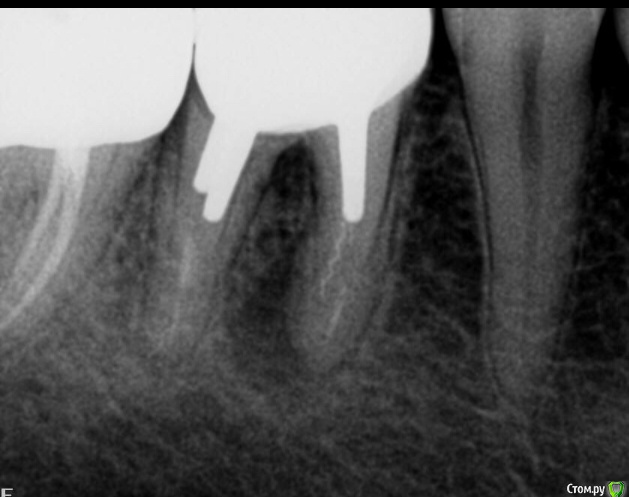

NNF Опубликовано 6 июля, 2020 Поделиться Опубликовано 6 июля, 2020 Здравствуйте уважаемые доктора! разболелся зуб под коронкой на снимке видно воспаление под корнем и ещё остаток инструмента в канале, подскажите возможно ли сохранить зуб или только удаление и потом имплантат ? Ссылка на комментарий

St. Опубликовано 6 июля, 2020 Поделиться Опубликовано 6 июля, 2020 В этом зубе помимо коронки стоят массивные штифты в каналах. Гипотетически шанс побороться за зуб есть, но работа сложная , дорогая и не прогнозируемая. То есть если Вы принимаете решение пробовать сохранить зуб, то должны понимать что сразу что то пообещать и спланировать тут не получится. доктор будет снимать коронку, доставать штифты. После этого оценивать что осталось от зуба и нет ли трещин в корнях. Если от зуба осталось мало или нашли трещину, то удаление. Если все ок, тогда перелечивание каналов и новая коронка. Ссылка на комментарий

NNF Опубликовано 6 июля, 2020 Автор Поделиться Опубликовано 6 июля, 2020 Спасибо большое за оперативный ответ, а как Вы считаете воспаление произошло из-за плохой пломбировки каналов и сломанного инструмента?зуб болит очень сильно, ибупрофен особо не помогает. Ссылка на комментарий